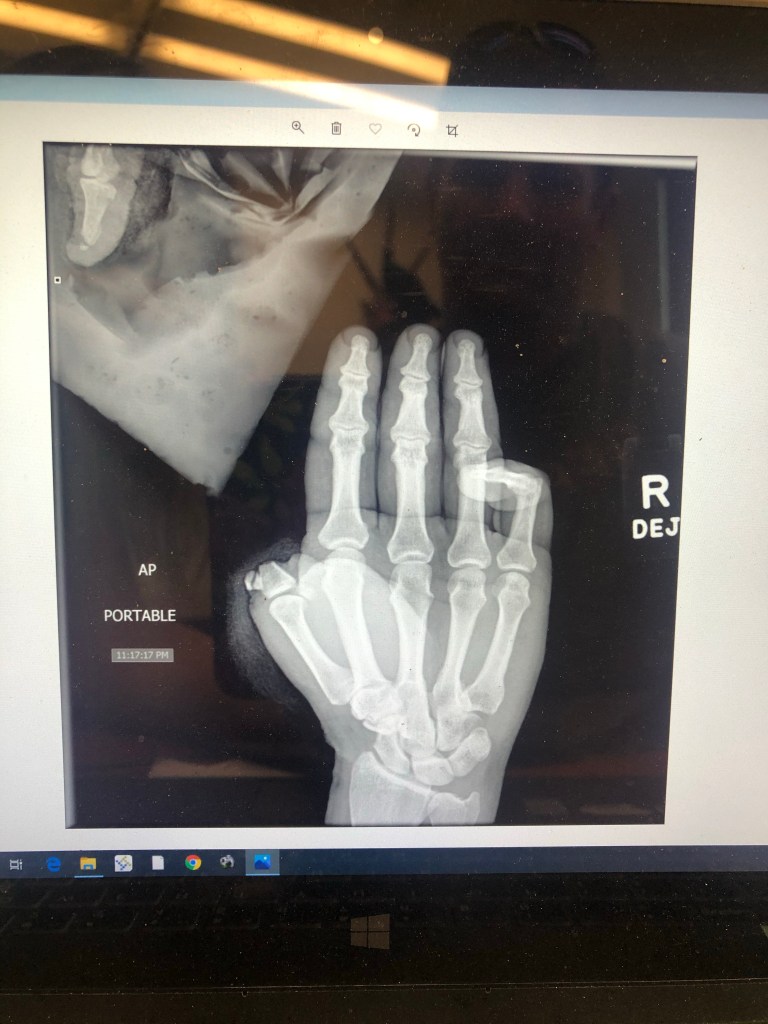

So you want to marry a cowboy? Just so you know- there could be this-

Yep. That happened. All of which is fairly self-explanatory- Here are the key points:

-Cowboy is a team roper. He is a heeler. A damn good one too.

-Rope coils remove body parts… similar to an auger to a farmer’s arm is a popped coil to a cowboy’s thumb.